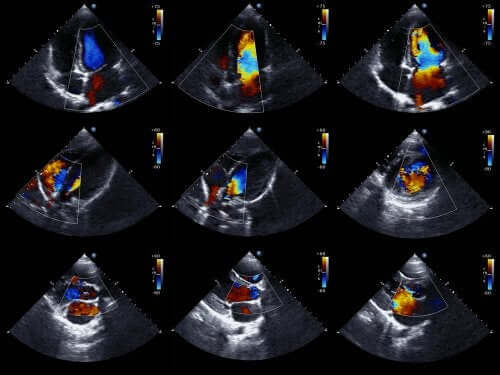

L’échocardiogramme est un examen médical très utilisé, car il permet d’obtenir des images du cœur en mouvement. On peut ainsi évaluer l’état des cavités du cœur et leur mouvement, et donc confirmer ou infirmer la présence d’une ischémie.

On peut aussi évaluer la taille du cœur, sa force et l’état des parois qui délimitent ses chambres. De plus, il s’agit d’un examen non invasif qui ne présente aucun risque pour le patient. En effet, cet examen emploie des ultrasons pour obtenir les images du cœur.

L’absence d’altérations dans la mobilité des parois cardiaques exclut la présence d’une ischémie importante. D’autre part, l’existence d’anomalies peut indiquer autre chose qu’un SCA. C’est donc pour cette raison qu’il faut évaluer à la fois les résultats des examens et les symptômes.